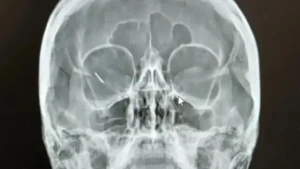

На 07.11.2025 г. около 11,00 ч., в района на площад „Георги Измирлиев“ в центъра на гр. Благоевград, била нападната И.И., на 37 години. На жената били нанесени множество прободни рани в шията, в областта на гръдния кош и в лявата сърдечна област, както и по лявата ръка, с остър предмет – нож.

Пострадалата е била транспортирана за оказване на медицинска помощ в тежко състояние и с опасност за живота. Оперирана е по спешност и стабилизирана. Извършителят на деянието – 33-годишният Г.М., се е предал на органите на реда.